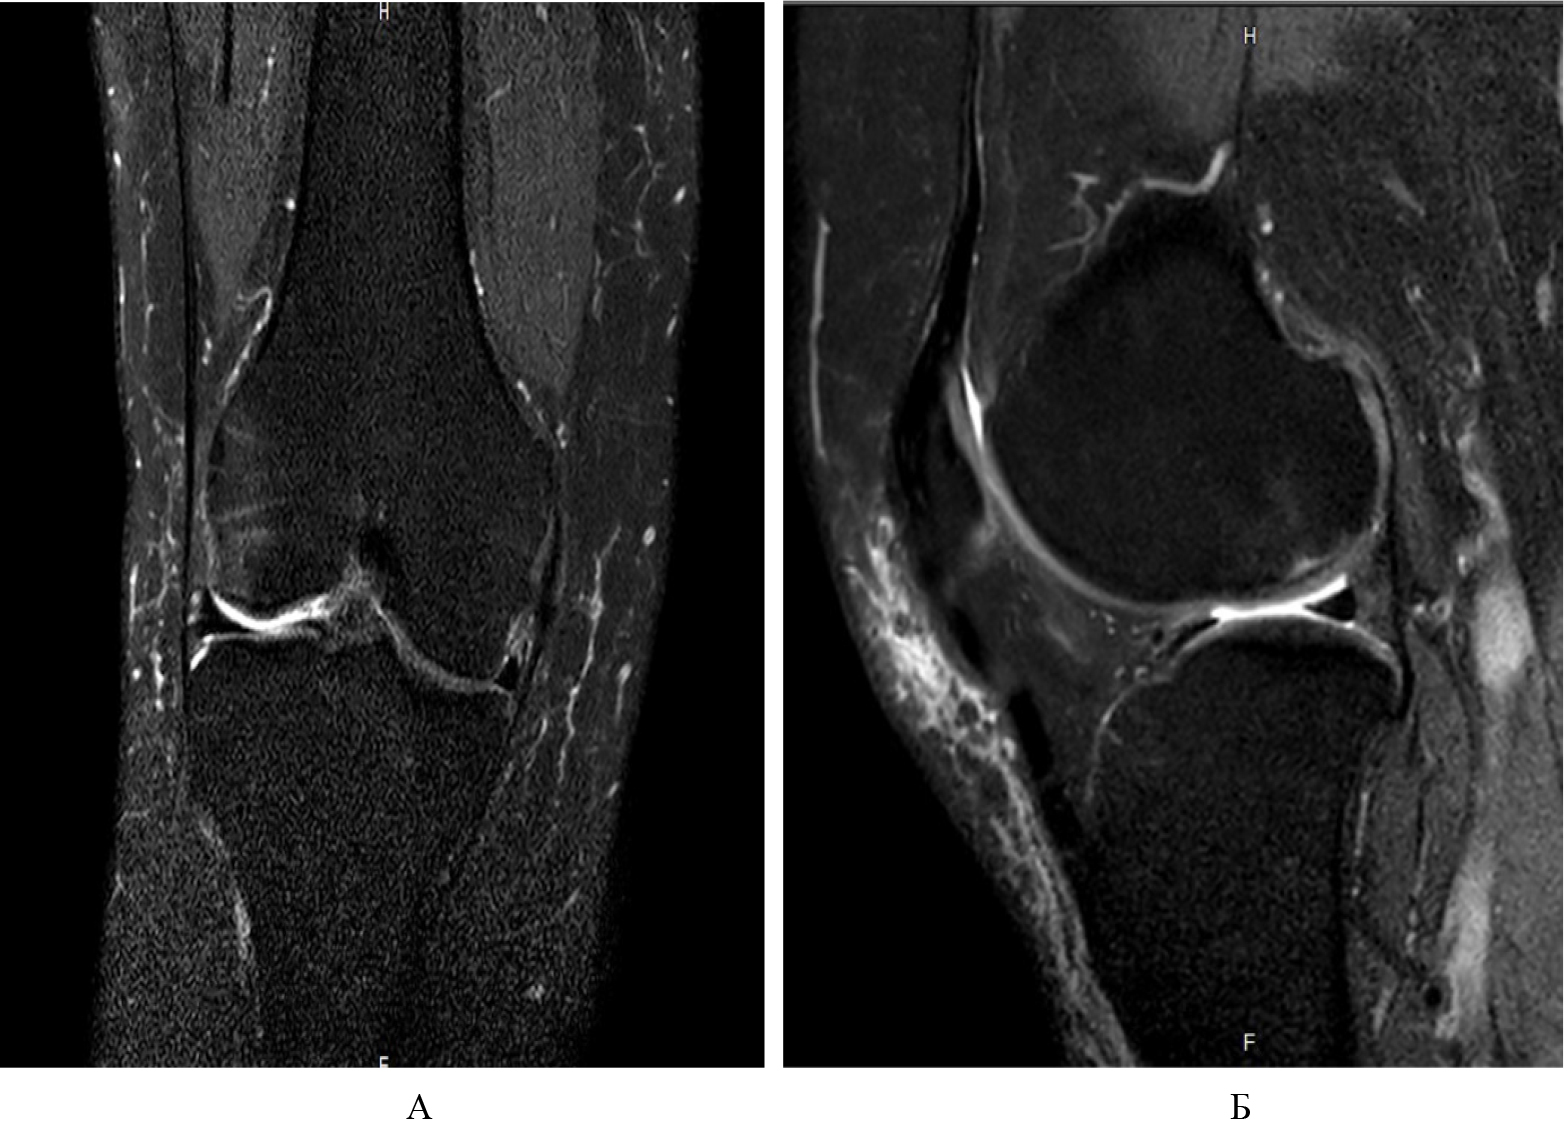

Объективным показателем регресса болевого синдрома и нормализации клеточного метаболизма субхондральной кости в результате устранения ишемии костного мозга являлось значительное сокращение площади или вовсе исчезновение зон трабекулярного отека костного мозга, что подтверждалось уменьшением линейных размеров гиперинтенсивных участков по данным МРТ. Зона некротического очага по своим линейным характеристикам осталась прежней (рис. 5).

Рис. 5. Регресс признаков ишемии и трабекулярного отека костного мозга: А, Б – прямая и боковая проекции на Т2-взвешенных изображениях